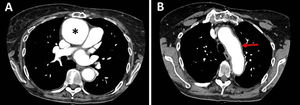

A 54-year-old woman diagnosed with end-stage idiopathic dilated cardiomyopathy underwent heart transplantation (HT). The immediate postoperative period elapsed without complications. One month later, the patient attended a follow-up appointment complaining of nonspecific chest pain and sternal wound discomfort. She was diagnosed with a postoperative mediastinal collection, after undergoing a chest computed tomography (CT) which showed an encapsulated collection extending from the superior vena cava to the anterior portion of the right atrium and right ventricle, and surrounding the aortic root. Antimicrobial treatment was not prescribed because there were no signs of infection. Cyclosporine, mycophenolate mofetil and prednisone were continued. The patient remained asymptomatic. Eight years after transplantation, a scheduled transthoracic echocardiography (TTE) described a saccular aneurysm of the ascending aorta, measuring 55mm×64mm, and significant aortic wall thickness. No vegetation or aortic valve dysfunction were observed. The aortic arch, the descending aorta and the left ventricular systolic function were normal. A CT angiography confirmed the aneurysm of the ascending aorta, which was located immediately above the aortic suture. Signs of aortitis were also seen (Fig. 1A and B). The patient mentioned slight weight loss and dyspnea on exertion, but denied having fever. On physical examination there were no stigmata of infective endocarditis. The leukocyte count was within normal range and the C-reactive protein was normal. Blood cultures were sterile. Tuberculosis, syphilis and autoimmune inflammatory disorders were excluded. The aortic aneurysm was excised and a tubular prosthesis was placed.